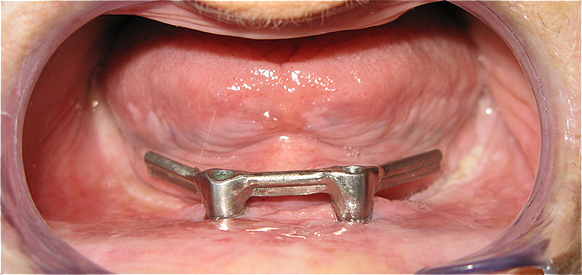

Caso 3 - Desdentado total reabilitado com prótese acrílica removível inferior, barra e clips para retenção e estabilidade

![]() |

![]() ![]() |